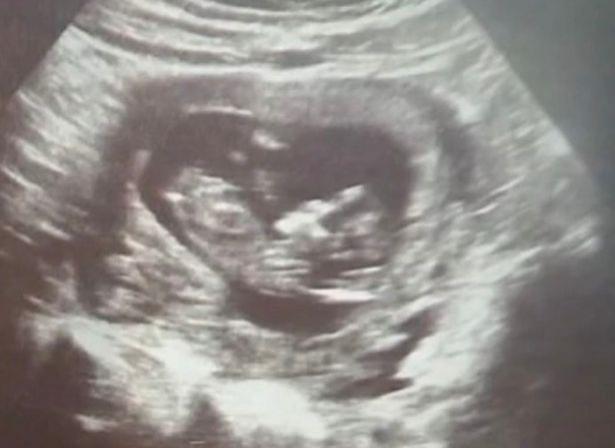

Şi-a pus bebeluşii la congelat imediat după naştere. Mama din Franţa mai avea 9 copii acasă